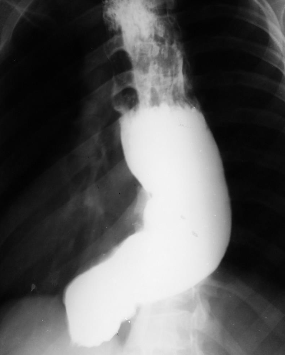

Hernie hiatală

Hernie hiatală prin alunecare

Hernie hiatală prin rostogolire

Hernie hiatală - brahiesofag